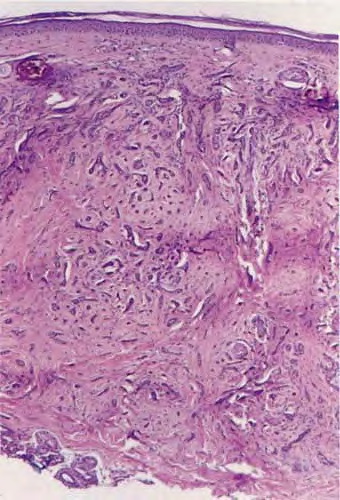

MICROCYSTIC ADNEXAL

CARCINOMA

MAC is also known as syringomatous carcinoma and sclerosing sweat duct carcinoma.

MAC is a rare, locally aggressive tumor with a high potential for local recurrence.

MAC usually presents in elderly individuals as a solitary, slowly growing, firm, indurated plaque on the face, particularly around the upper lip or orbit. For unclear reasons, the tumor tends to occur on the left side of the face. Lesions may occasionally be found on extra-facial locations, including the nipple, axilla, and lower extremities.